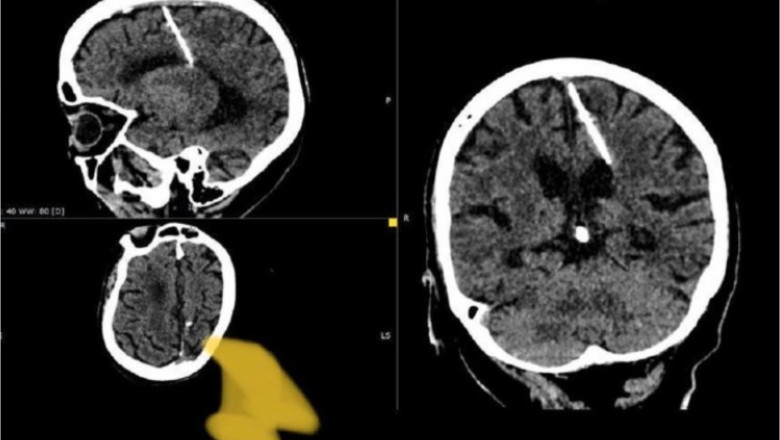

Ministerul Sănătății din regiunea Sahalin a scris pe Telegram că radiologii locali au descoperit un ac de trei centimetri cu ajutorul unei radiografii. Postarea nu dezvăluia când doctorii au făcut această descoperire, dar preciza că incidentul a avut loc în 2023.

Acul a fost descoperit în lobul parietal stâng al femei a cărei nume nu a fost dezvăluit. Oficialii au spus că acul a rămas în creierul femeii încă de la naștere, atunci când doctorii cred că părinții ei au încercat să o omoare.